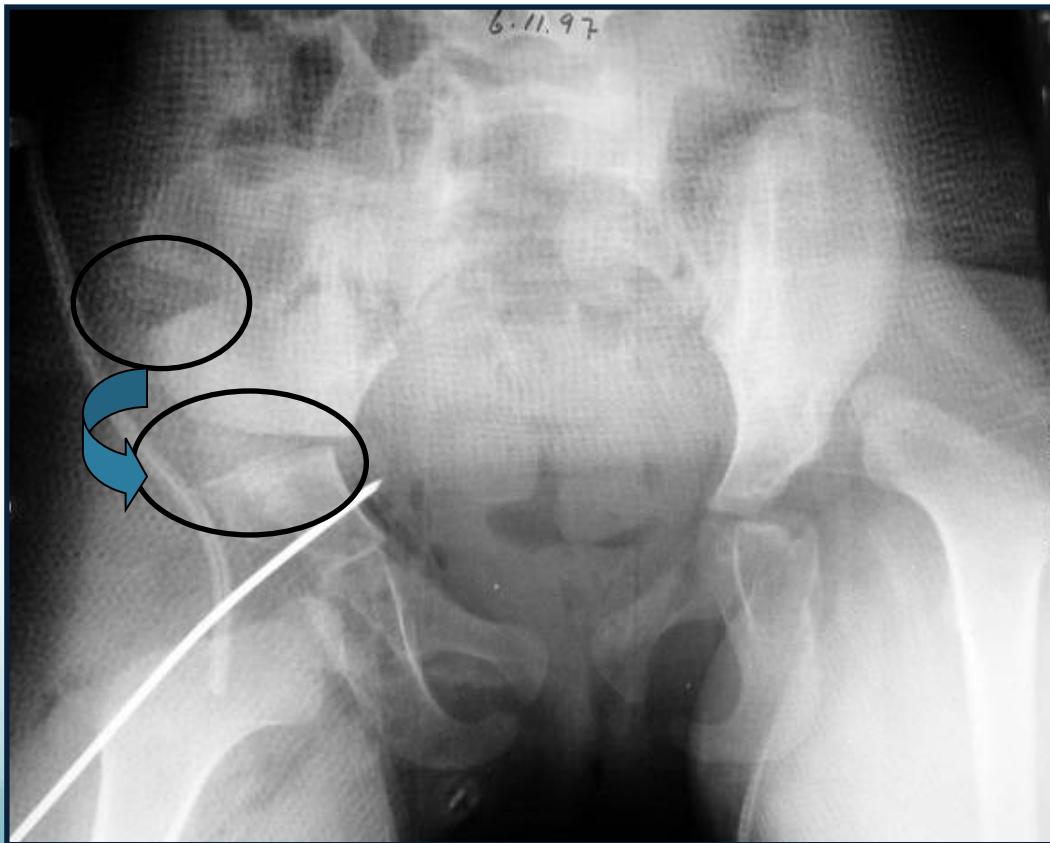

Radiology z

- After 3 months: more reliable

- Early infancy: not reliable - U/S better

- AP abduction view

- Long axis of femur normally passes through acetabulum

After 6 months:

- Clearly shows dislocation

- Size of femoral head ossific center

- Horizontal line through the tri-radiate cartilage

Position Assessment:

- Dislocated: Above the horizontal line

- Normal: Below the horizontal line

Radiographic Measurements

Perpendicular line from edge of acetabulum:

- Dislocated: Lateral to perpendicular line

- Normal: Medial to perpendicular line

Acetabular angle (acetabular index):

- Normal: ≤ 25°

- Dislocated: > 35°

Shenton’s line: